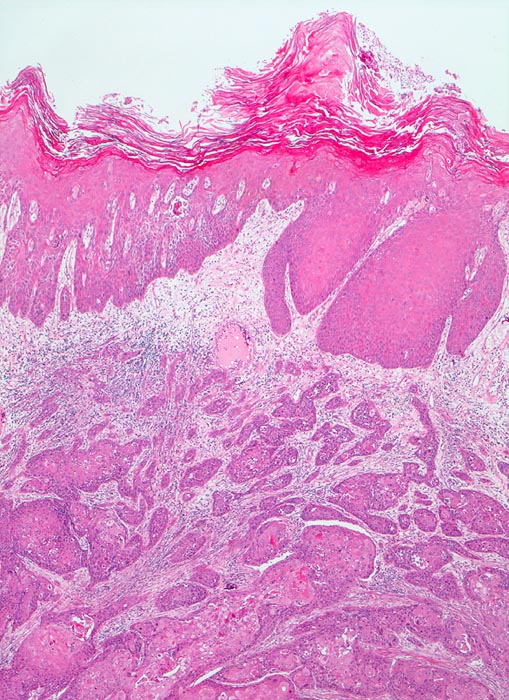

PathoPic – image database / PathoPic ID 3231 - Verhornendes Plattenepithelkarzinom

Verhornendes Plattenepithelkarzinom

Harnblase

Die Harnblasenoberfläche wird ausgekleidet durch ein stark verhornendes Plattenepithel mit Atypien. Das darunterliegende Stroma wird infiltriert von plattenepithelial differenzierten Tumorzellsträngen.

Paraplegie seit 16 Jahren.

Plattenepithelkarzinome treten als Folge chronischer Entzündungen auf. (Dauerkatheterträger, Zyklophosphamid Langzeittherapie mit Zystitis, Bilharziose).